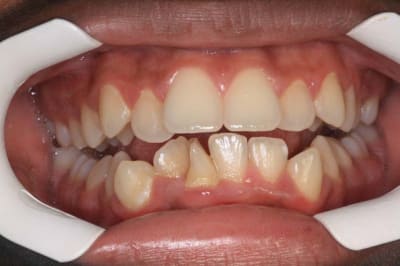

Je ne cherche pas à polémiquer, je pose simplement la question :

Tu penses arriver à traiter des cas comme ceux là, avec des gouttières ?

P.S.: la faiblesse des gouttières est la correction des rotations

Img 3218 l9hvjz - Eugenol

Img 3610 pmoxur - Eugenol

01 ukhwbq - Eugenol